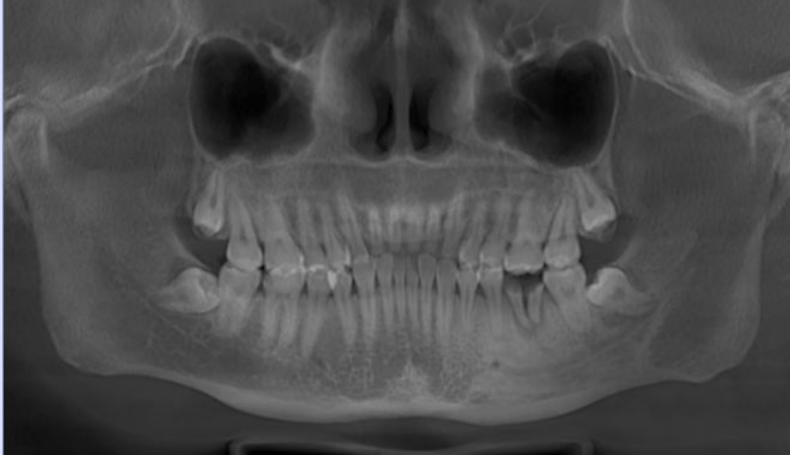

自体牙移植让智齿等“闲置牙”变废为宝,但需医生通过CBCT等检查精准评估。成功移植后,牙齿能像原生牙一样感知咀嚼力度,真正实现“以牙补牙”的理想效果。